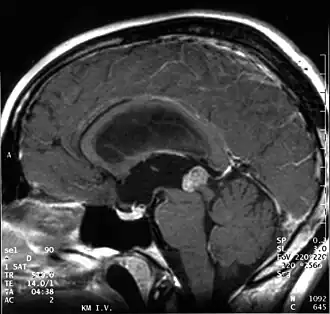

Aufgrund ihrer typischen Lage behindern papilläre Tumoren der Pinealisregion häufig den Fluss der Cerebrospinalflüssigkeit, was zu einer Erhöhung des Hirndrucks führen kann. Kopfschmerz, Übelkeit und Erbrechen sind unspezifische Symptome. Durch Druck des Tumors auf die Vierhügelplatte treten nicht selten Störungen der Okulomotorik mit Doppelbildern auf (Parinaud-Syndrom). In der Kernspintomographie stellen sich papilläre Tumoren der Pinealisregion als kontrastmittelanreichernde Raumforderungen dar.